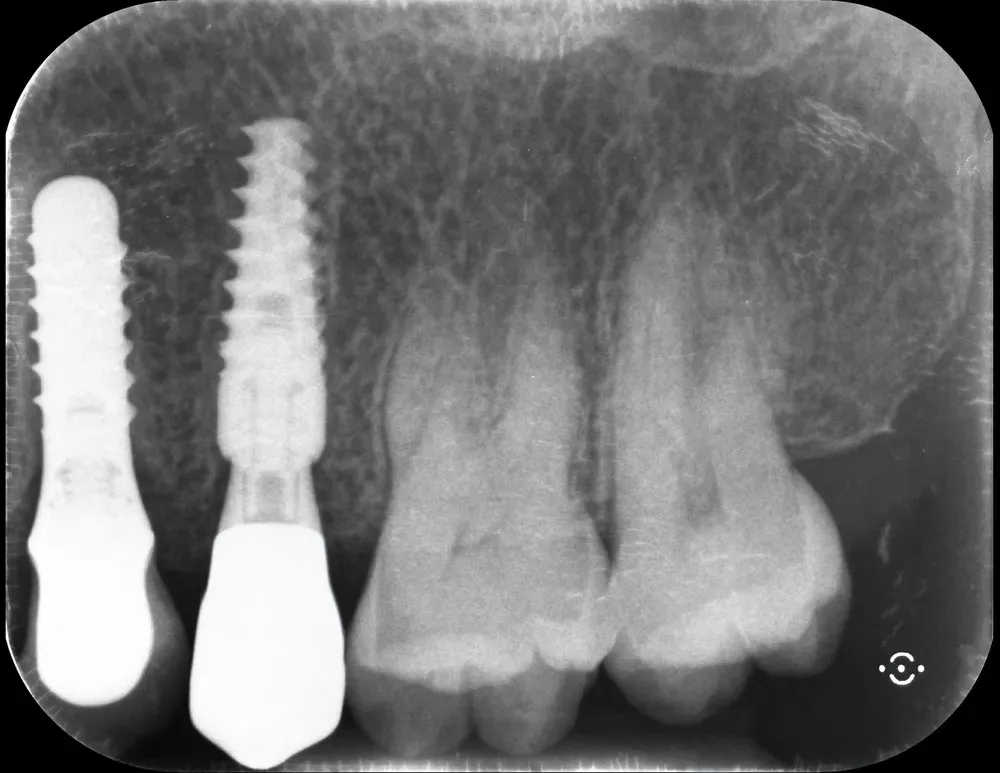

Ponti e full-arch: l’obbligo dei Multi-Unit Abutment

Nelle riabilitazioni complesse — ponti estesi, full-arch (arcate complete) — l’uso dei Multi-Unit Abutment (MUA) non è un’opzione. È una necessità clinica nella maggioranza dei casi, con l’eccezione degli impianti dritti ad esagono esterno. È particolarmente importante per tutte le connessioni interne, e in modo assoluto per le coniche. Ed è necessario anche se gli impianti sono dritti, mentre per i “tilted” (impianti inclinati) sarebbe addirittura impossibile riuscire a realizzare una qualsiasi protesi, anche imprecisa, senza i MUA.

I MUA risolvono tre problemi in un colpo. Eliminano le tensioni meccaniche durante l’inserimento delle strutture, evitando stress sull’osso crestale. Garantiscono il sigillo biologico seguendo il principio one abutment-one time: l’abutment transmucoso viene posizionato una sola volta. E spostano l’interfaccia protesica in zona coronale, più accessibile all’igiene e fuori del complesso sovracrestale. .

Il principio one abutment-one time (Luigi Canullo (2010) https://pubmed.ncbi.nlm.nih.gov/21180681/) è geniale. Abrahamsson e collaboratori nel 1997 hanno dimostrato sui beagle che la disconnessione ripetuta dell’abutment compromette la barriera mucosale e causa riassorbimento osseo aggiuntivo (https://doi.org/10.1111/j.1600-051x.1997.tb00230.x). La meta-analisi più recente di Vatėnas e Linkevičius ha quantificato il danno: 0,4 mm di perdita ossea marginale in più nel gruppo con disconnessioni ripetute (https://pubmed.ncbi.nlm.nih.gov/34528906/). Può sembrare poco. Ma in un contesto dove ogni decimo di millimetro conta per la sopravvivenza a lungo termine, è un costo evitabile.

Mi dispiace ammetterlo, ma inizialmente ero contrario ai MUA e li volevo evitare quando riuscivo a non usare impianti tilted nei full-arch. Sbagliavo. Nelle arcate complete, e spesso anche nei ponti più corti, i MUA sono indispensabili. L’alternativa è usare impianti dritti con connessione a esagono esterno — che trasforma il problema in una soluzione efficace. Oppure interporre i MUA per convertire l’esagono interno in esterno. In entrambi i casi, la biologia ci chiede di minimizzare le disconnessioni.